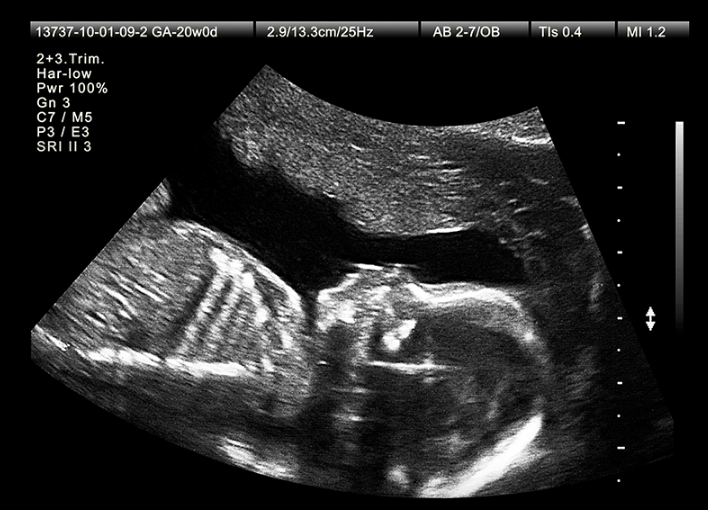

Kỹ thuật siêu âm 2D được ra đời sớm nhất để kiểm tra, theo dõi sự phát triển của thai nhi và cả mẹ.

Sau khi phát hiện mình có thai tại nhà bằng que thử thai, bước tiếp theo mẹ cần thực hiện tại bệnh viện là siêu âm 2D nhằm xác định lại chính xác việc có thai, thai nằm ở vị trí trong hay ngoài tử cung, số lượng thai, tuổi thai và ngày dự sinh.

Hình ảnh của siêu âm 2D hiển thị mặt cắt của cơ thể trên không gian 2 chiều. Trên hình ảnh, những khoảng tối màu chứa nước, dịch, máu, trong khi những vùng màu xám đến trắng thể hiện những vùng cấu trúc mô cơ thể, màu càng sáng thì cấu trúc càng đặc.

Dựa trên hình ảnh siêu âm 2D ghi được, bác sĩ có thể chẩn đoán về tình hình phát triển của thai nhi, tuổi thai, phát hiện các dị tật thai nhi bẩm sinh (nếu có), đánh giá tình trạng của mẹ (nước ối, bánh nhau,...).

Siêu âm thai 2D là kĩ thuật chẩn đoán không xâm lấn, nên an toàn và hoàn toàn có thể cung cấp đầy đủ thông tin chính xác về thai nhi. Tuy nhiên, mẹ sẽ cần sự giải thích và phân tích của bác sĩ mới có thể hiểu được hình ảnh của siêu âm 2D.